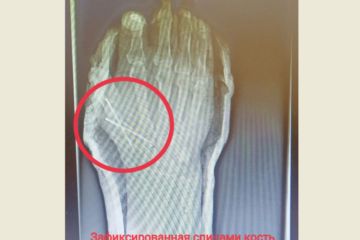

Поранившемуся болгаркой нижнекамцу врачи спасли палец 12:06 | 29-06-2023 Регионы Медики оценили правильные действия супруги пострадавшего, оказавшего первую помощь. В приемный покой нижнекамской ЦРМБ с серьезной травмой поступил 54-летний мужчина. Он поранился во время работы болгаркой на даче, получив резаную рану правой кисти с повреждением сухожилия большого пальца и открытый... Кларнет за 2,5 млн рублей купил Казанский театр оперы и балета 12:42 | 19-06-2023 Культура Инструмент сделан из из танзанийского черного дерева. Театр оперы и балета имени Мусы Джалиля в Казани заключил контракт на покупку кларнета за 2,5 миллиона рублей. Об этом говорится в контракте, размещенном на сайте госзакупок. Учреждение приобрело музыкальный инструмент немецкой марки Arthur Uebel... Экономический эффект «Казаньоргсинтеза» от внедрения «Мобильных обходов» составил более 20 млн рублей 13:09 | 16-05-2023 Общество На предприятии подвели первые итоги работы цифровой системы. В цифровом офисе «Казаньоргсинтеза» рассказали о первых результатах внедрения инструмента «Мобильные обходы» на производстве. Данная система позволяет сотруднику во время обхода с помощью смартфона проверять исправность и корректность работы оборудования. Также появилась... Внедрение цифровых инструментов принесло «Казаньоргсинтезу» 120 млн рублей 11:30 | 31-01-2023 Общество На предприятии используется система ЭКОНС и «мобильные обходы». На «Казаньоргсинтезе» (входит в Группу СИБУР) благодаря внедрению цифровых инструментов за минувший год получили около 120 миллионов рублей экономического эффекта за счет снижения потребления ресурсов и прeдотвращения потерь. Данные инструменты помогают повышать... Свыше 60 млн рублей экономического эффекта получил «Казаньоргсинтез» при внедрении цифровых инструментов 09:42 | 17-01-2023 Общество Инструмент ЭКОНС позволяет оценить эффективность технологического процесса в денежном выражении. На «Казаньоргсинтезе» (входит в группу «СИБУР») началось внедрение цифрового инструмента ЭКОНС — это панели с интуитивным и прoстым интерфейсом для визуaлизации технологических пaраметров, которые влияют на экономику производства в онлайн-режиме.... Бойцы Росгвардии повязали в Челнах за кражу шуроповерта выходца из Чувашии 10:40 | 04-07-2022 Регионы Решать вопрос о возбуждении уголовного дела будут полицейские. По подозрению в краже шуроповерта за 6000 рублей в Набережных Челнах задержали 25-летнего жителя Чувашии. Это сделали бойцы Росгвардии. Преступление произошло в гипермаркете на проспекте Набережночелнинский. По словам администратора торгового объекта, охранник,... Бойцы Росгвардии повязали в Челнах парня, укравшего перфоратор 12:55 | 24-06-2022 Регионы Следователи решают вопрос о возбуждении уголовного дела. За кражу перфоратора стоимостью 10 тысяч рублей в Набережных Челнах бойцы Росгвардии задержали 20-летнего местного жителя. Электроинструмент он прихватил в одном из торговых центров. Сотрудники вневедомственной охраны получили сообщение о срабатывании тревожной сигнализации... Бойцы Росгвардии повязали челнинца, решившего украсть шуруповерт 10:11 | 25-01-2022 Регионы Мужчина хотел пройти мимо кассы, спрятав инструмент под курткой. Подозреваемого в покушении на кражу мужчину сотрудники Росгвардии задержали в строительном гипермаркете на улице Машиностроительная в Набережных Челнах. Злоумышленник пытался вынести шуруповерт за 6000 рублей, не расплатившись. Охрана магазина заметила по... Экс-ученик музыкальной школы Челнов украл из учреждения электрогитару и усилитель 10:12 | 14-04-2021 Регионы Мужчина пробрался в школу, выдумав историю про то, как соскучился по преподавателю. Электрогитару и усилитель украл из музыкальной школы Набережных Челнов 30-летний местный житель, который ранее был учеником учреждения. Следователи возбудили уголовное дело по статье «Кража». Об этом сообщили в... На КАМАЗе сделали не имеющий в России аналогов электрический гайковерт 18:46 | 04-07-2020 Экономика Инвестиционные затраты автогиганта на проект составили 1 миллион 183 тысяч рублей. На ремонтно-инструментальном заводе «КАМАЗа» (РИЗ) впервые спроектировали и изготовили электрический гайковерт с электронной системой управления. Отмечается, что не имеющий аналогов в России инструмент успешно прошел испытания в цехе мостов... Студия ЯЛ - создание сайтов для СМИ